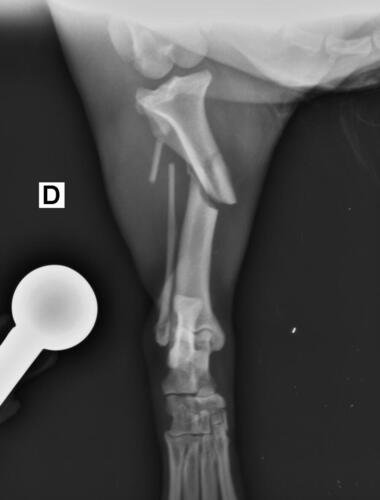

Olá, me chamo Jacqueline sou a mãe do chokito de 4 patas 🐶. No dia 07/02/2025 chokito foi atropelado em frente a minha casa, onde resultou no quadril dele quebrado e a patinha direita traseira quebrada tbm (a tíbia). Quem atropelou ele não parou pra prestar socorro a ele, e mto menos quis saber oque havia acontecido. Chokito foi atropelado na frente dos meus filhos, duas crianças um autista de 5 anos e uma criança de 3 anos, onde o acidente poderia ter acontecido com um deles, mas graças a Deus, Deus livrou eles, mas infelizmente o chokito não. Desde o dia 07 o chokito sofre de fortes dores constantes, onde ele não consegue se movimentar, para se alimentar ele precisa de ajuda, pra beber água, está com dificuldade em evacuar por conta das fortes dores que ele vem sentindo. Preciso de ajuda pra dar uma qualidade de vida pro chokito voltar a andar e parar de sentir dores constantes. A cirurgia ficou em torno de R$5,500 reais, um valor ao qual eu não consigo pagar, tudo tem sido mto caro, tenho gastado com remédios, Raio x, veterinário, já a cirurgia está mto a cima do que eu poderia pagar pra ajudar ele. Chokito é um cachorro que já foi abandonado e maltratado, pegamos amor e cuidamos dele, meus filhos sofrem por não poder brincar com o cachorro deles e ver o cachorro sempre gritando de dor é uma tristeza para todos nós. Por isso preciso de ajuda pra custear essa cirurgia que ele tanto precisa. Por favor quem puder me ajudar de alguma forma pra que ele volte a andar e parar de sofrer. Estou com meu coração dilacerado vendo ele sofrer sem poder fazer mais do que eu já estou fazendo que é cuidar dele. Cada dia que passa é mais tempo que ele passa sofrendo e agravando a situação que ele se encontra.